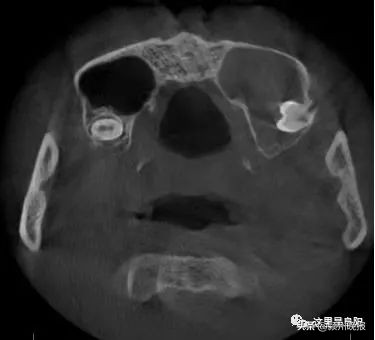

经检查

一颗智齿长到了他的鼻子里

小刘的智齿位于窦腔底部

与鼻子上颌窦仅一膜之隔

而这层膜比蛋壳还要薄